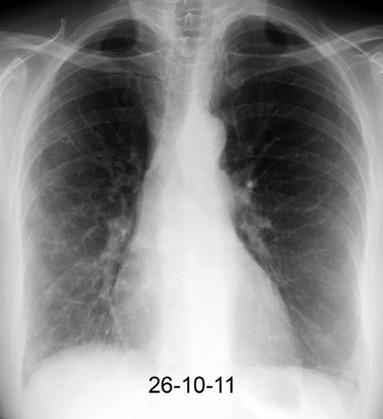

30 años

Borramiento de la banda PARA-aórtica por AdenoCa. de LII, no visible en 2005

Colapso de LII. TC: secreciones bronquiales.

Endoscopia tapón mucopurulento extraído